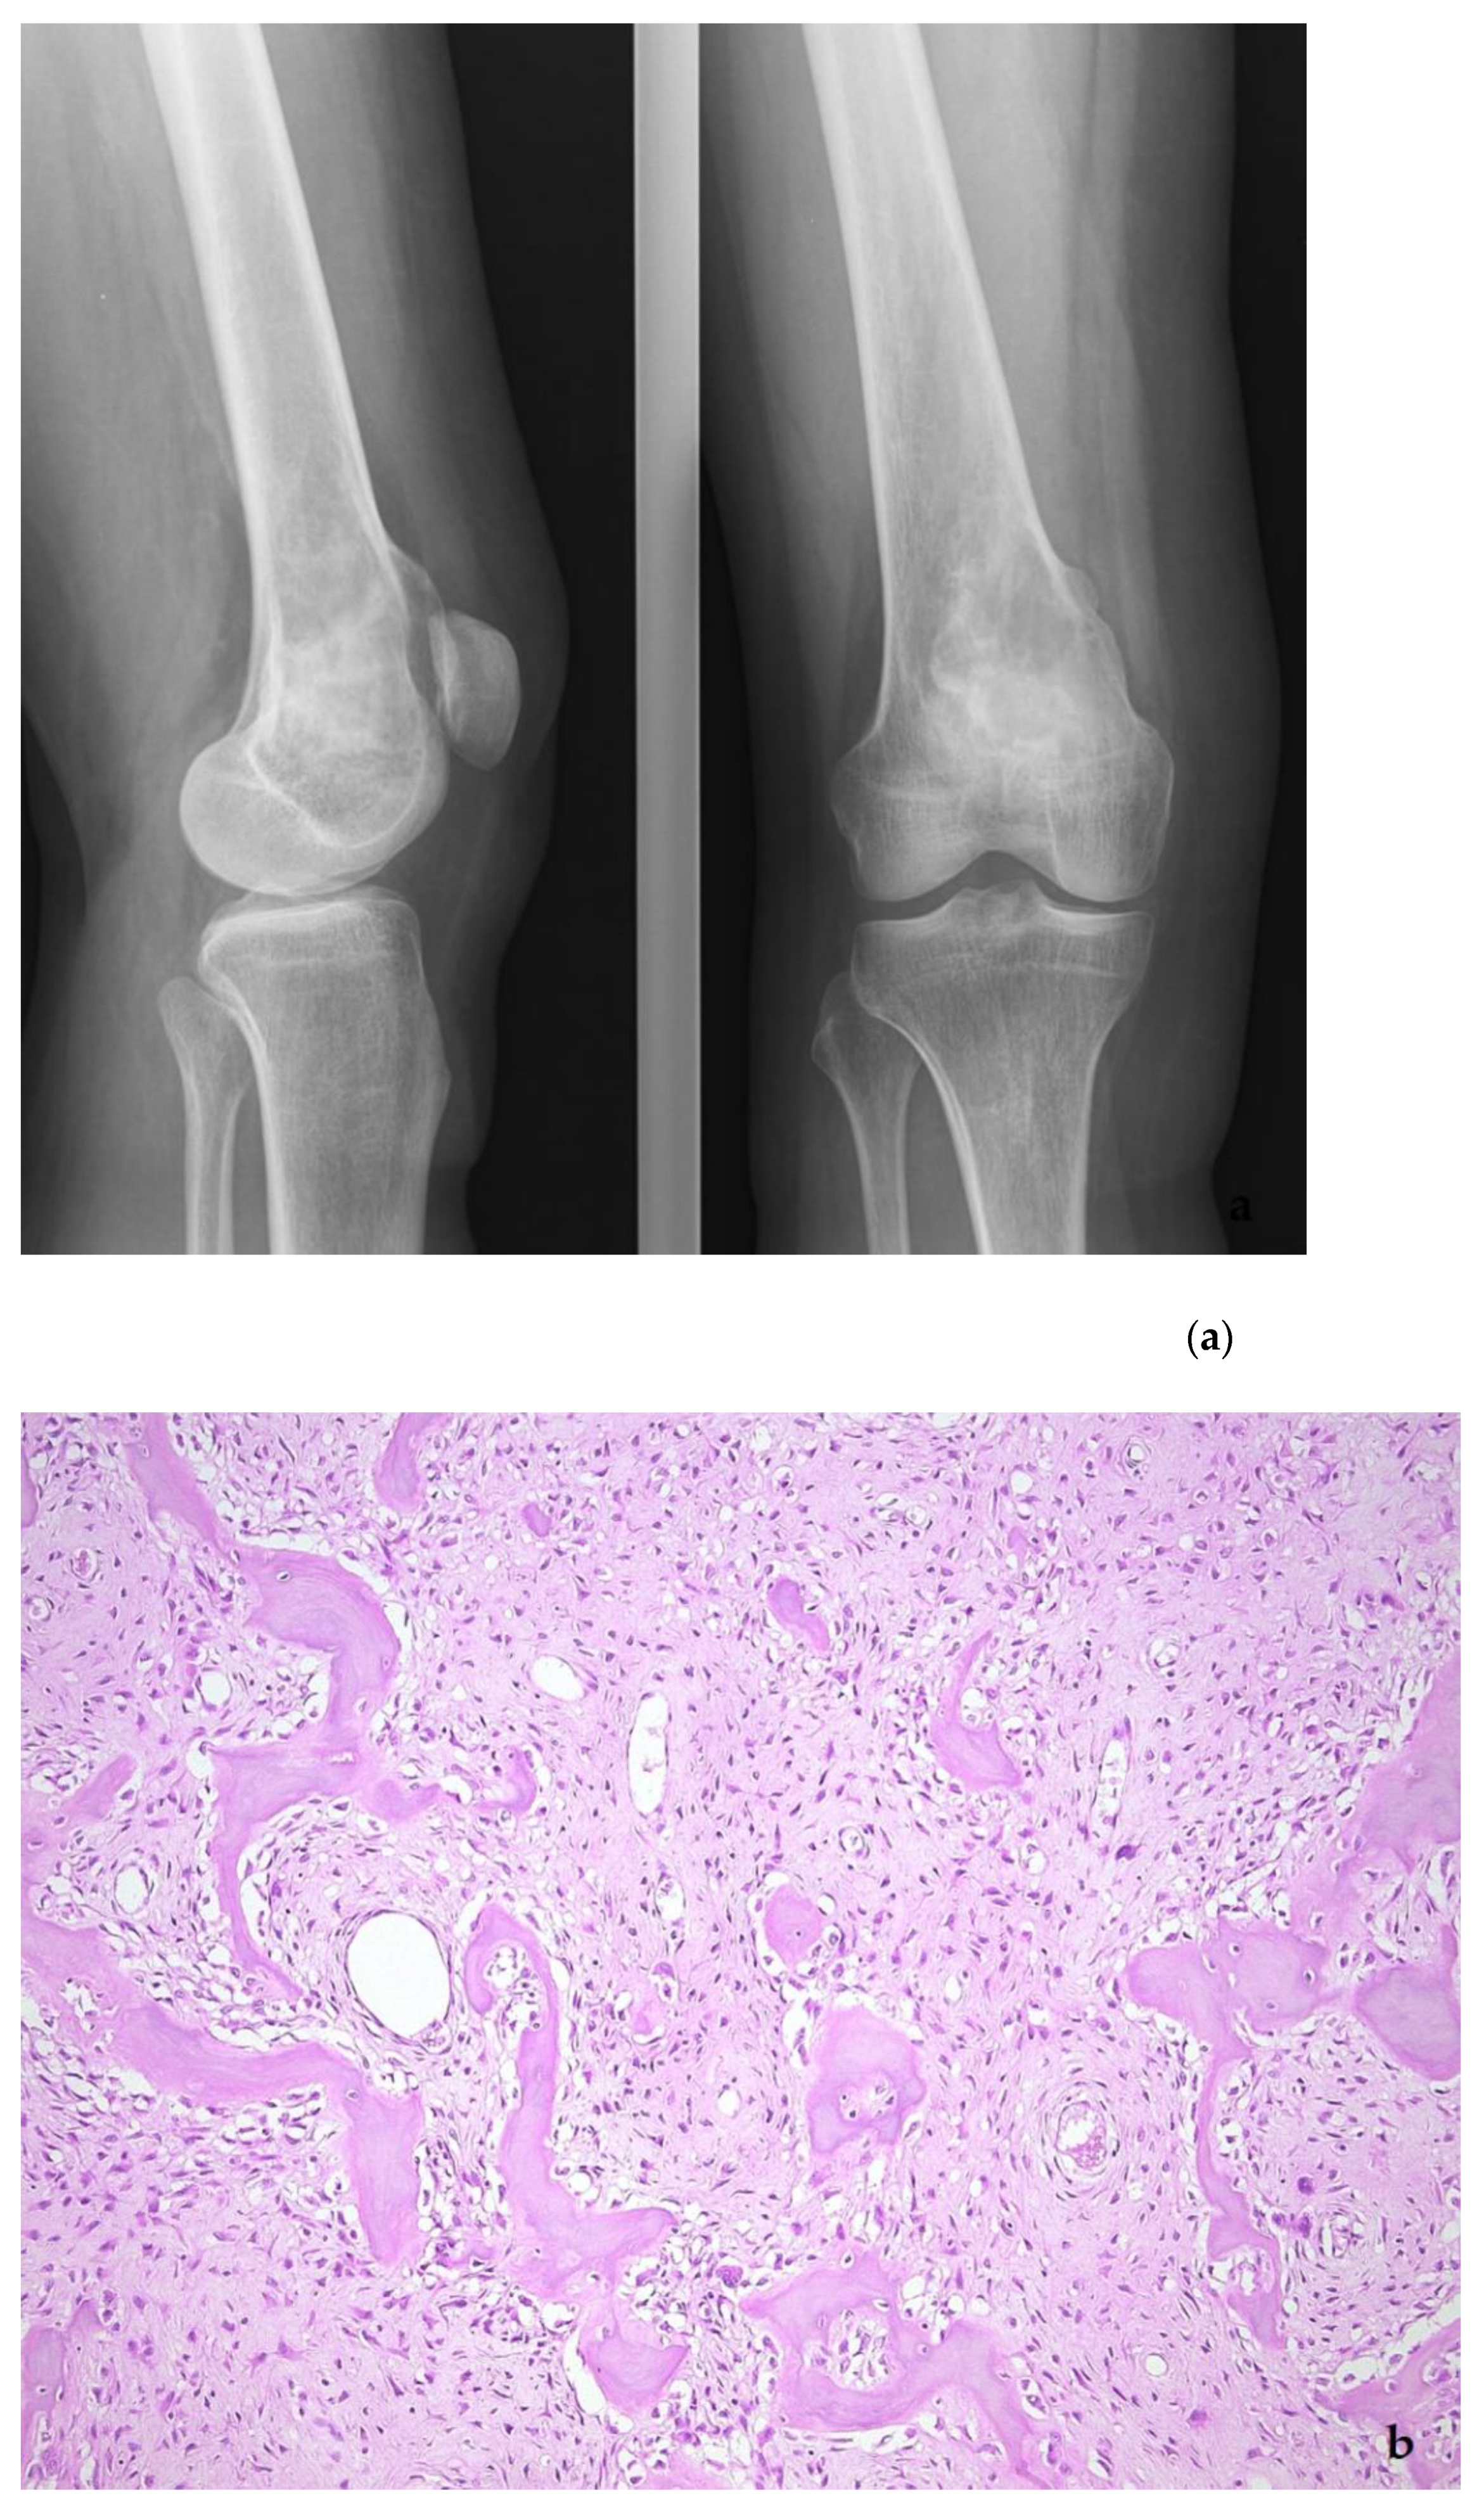

5. Low-Grade Osteosarcoma

- Wang, J.; Nord, K.H.; O’Donnell, P.G.; Yoshida, A. Parosteal osteosarcoma. In WHO Classification of Tumours Editorial Board. Soft Tissue and Bone Tumors; International Agency for Research on Cancer: Lyon, France, 2020; pp. 410–413. [Google Scholar]

- Yoshida, A.; Bredella, M.A.; Gambarotti, M.; Sumathi, V.P. Low-grade central osteosarcoma. In WHO Classification of Tumours Editorial Board. Soft Tissue and Bone Tumors; International Agency for Research on Cancer: Lyon, France, 2020; pp. 400–402. [Google Scholar]

- Dujardin, F.; Bui Nhuyen Binh, M.; Bouvier, C.; Gomez-Brouchet, A.; Larousserie, F.; de Muret, A.; Louis-Brennetot, C.; Aurias, A.; Coindre, J.M.; Guillou, L.; et al. MDM2 and CDK4 immunohistochemistry is a valuable tool in the differential diagnosis of low-grade osteosarcomas and other primary fibro-osseous lesions of the bone. Mod. Pathol. 2011, 24, 624–637. [Google Scholar] [CrossRef] [PubMed]